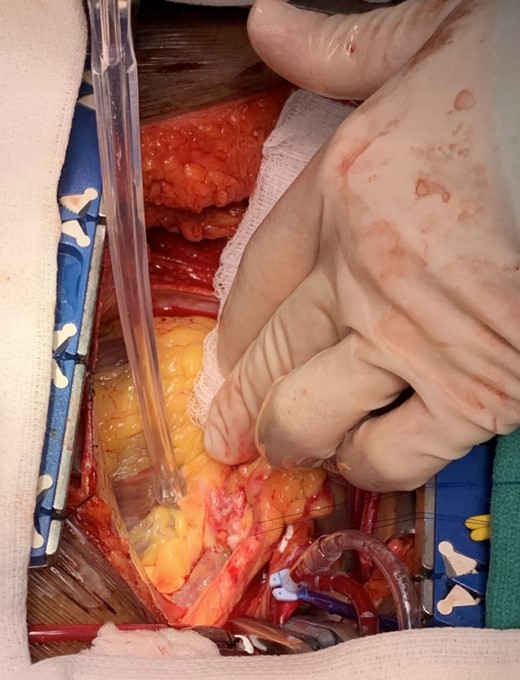

The patient was taken to the operating room and underwent a median sternotomy. The left radial and left internal mammary arteries (LIMA) were harvested in anticipation of LMCA ligation and bypass to the left circumflex and LAD. She was placed on cardiopulmonary bypass via standard central cannulation and the heart was arrested with antegrade and retrograde Del Nido cardioplegia. Although we were prepared to divide the pulmonary artery to provide for better exposure, we found it unnecessary. Medial retraction of the pulmonary artery provided adequate exposure of the distal LMCA. The aneurysm sac was opened and the orifices of the left main, circumflex and LAD were identified (Fig. 2). There was no thrombus within the aneurysm. There was a 10 mm by 12 mm oval aneurysmal defect with a distinct transition between normal arterial wall and the significantly attenuated aneurysmal segment. The aneurysmal defect was excised and a patch of the radial artery was used to reconstruct the superior wall of the LMCA (Fig. 3). No coronary bypasses were done. The patient separated from cardiopulmonary bypass easily. Transesophageal echocardiogram showed normal left and right ventricular function.

Intraoperative photo demonstrating the lumen of the distal left main coronary artery where it bifurcates into the circumflex and left anterior descending artery through the incised superior wall of the aneurysm.